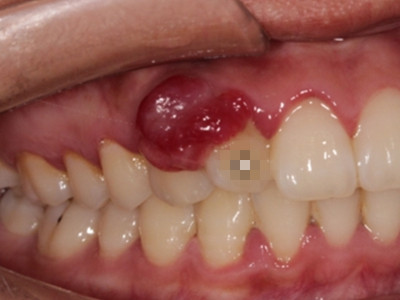

牙龈癌多源于牙间乳头及龈缘区,溃疡呈表浅、淡红,以后可出现增生。由于黏骨膜与牙槽突附着甚紧,较易早期侵犯牙槽突骨膜及骨质,进而出现牙松动,并可发生脱落。X线片可出现恶性肿瘤的破坏特征虫蚀状不规则吸收。

牙龈癌常发生继发感染,肿瘤伴以坏死组织,触之易出血。体积过大时可出现面部肿胀,浸润皮肤。

即使是早期的牙龈癌,原则上均应行牙槽突切除,而不仅仅是牙龈切除术。较晚期的应作下颌骨或上颌骨次全切除术。牙龈癌已侵入上颌窦者,应行全上颌骨切除术。一旦发生转移,即应行治疗性颈淋巴清扫术。